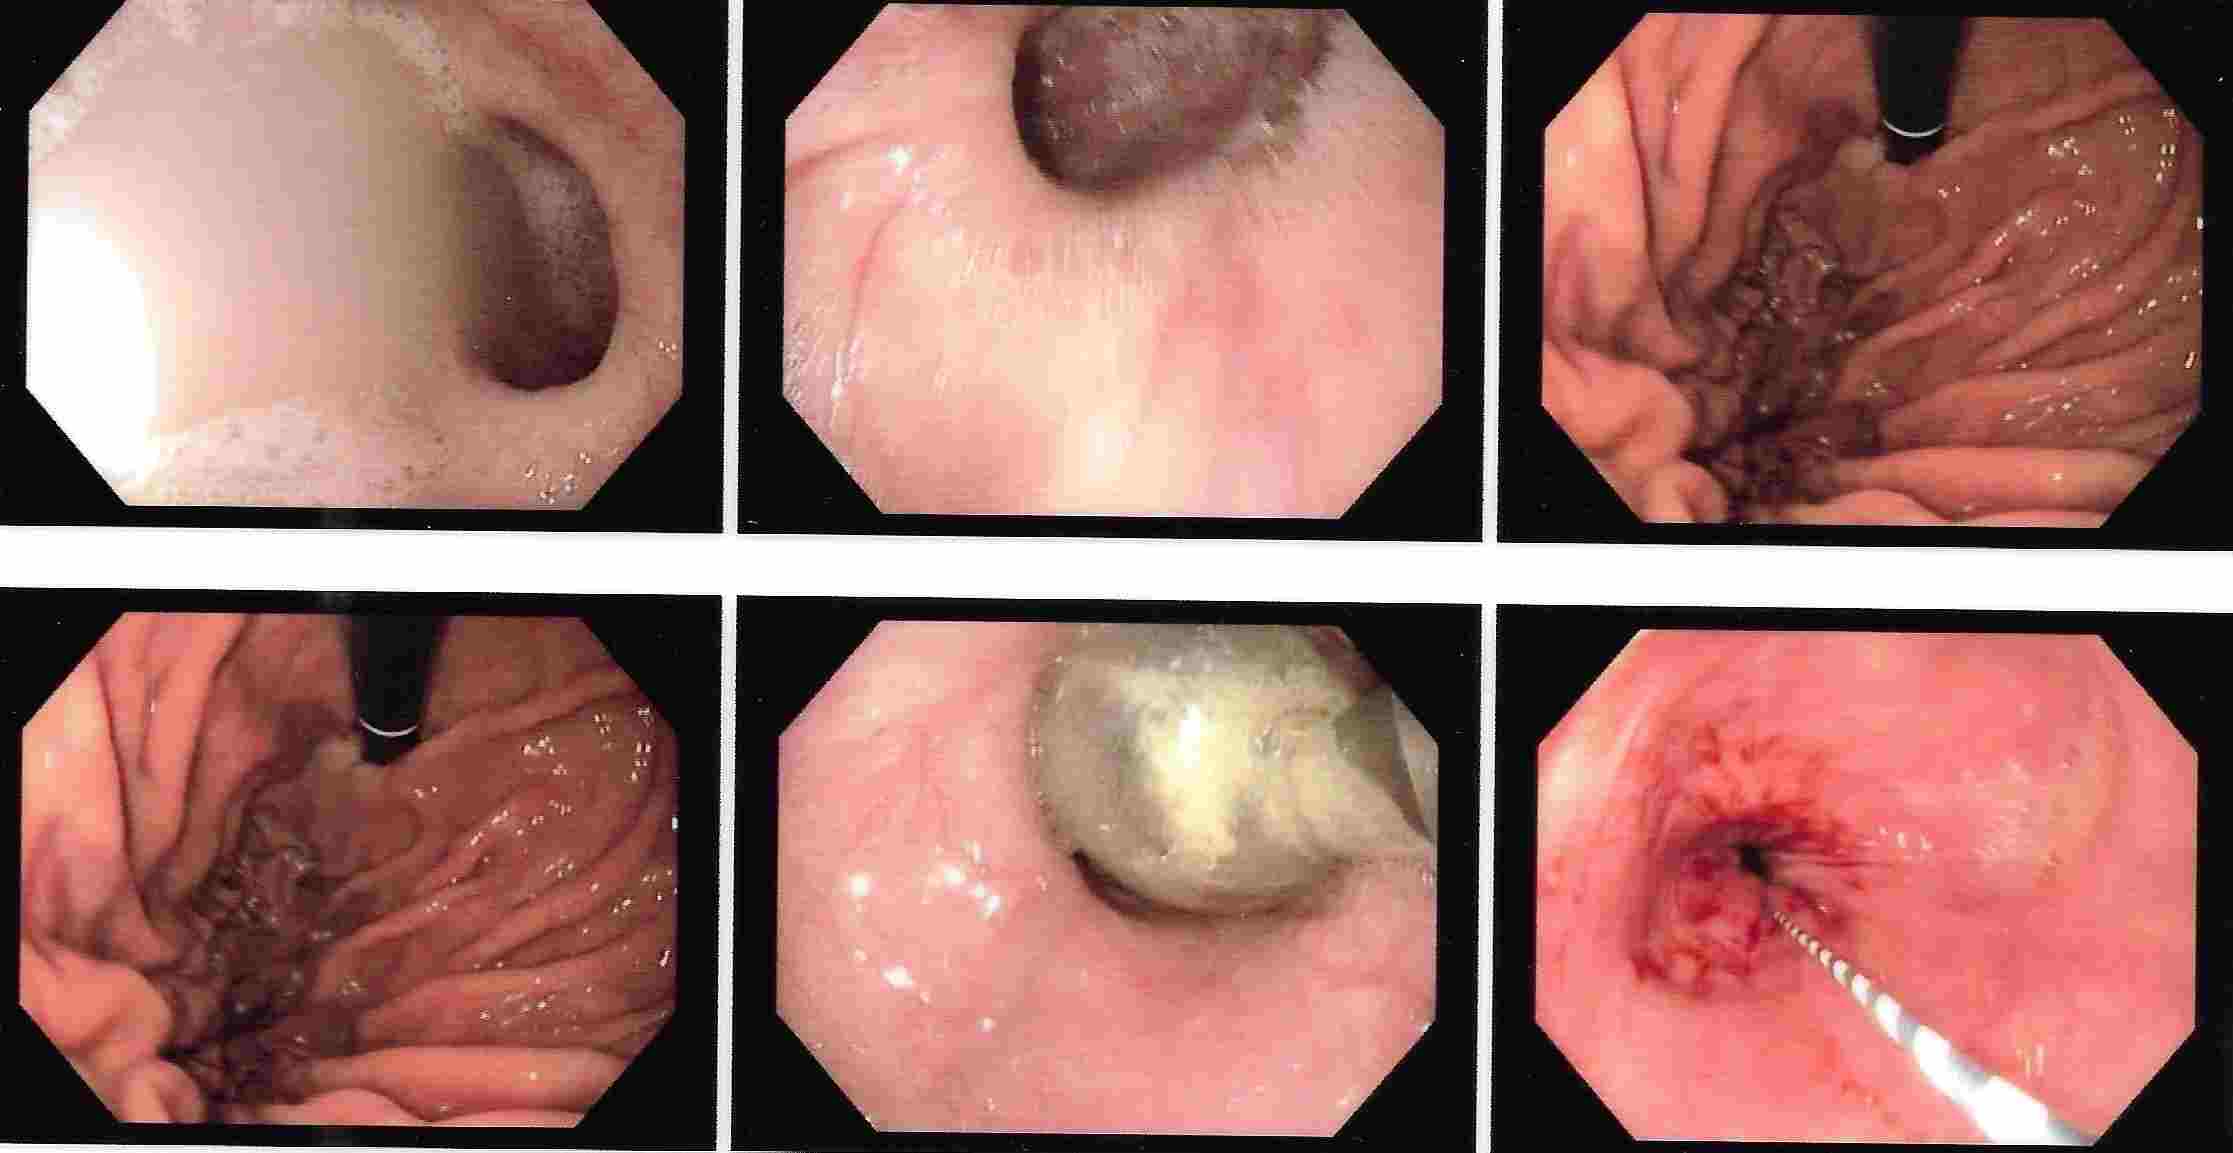

COLONOSCOPY

Colonoscopy is a procedure where the doctor can examine the lowermost part of the digestive tract

by a flexible instrument called as Colonoscope. Common indications for Colonoscopy are

7. Frank blood in the stool, occult blood in the stool or anaemia.

These conditions are seen more often in elderly people where Colonoscopy is essential for making an early diagnosis of cancer of the colon.

Colonoscopy is advocated for first blood relations of the patient who has got cancer of the colon.

Common mistake is to attribute blood in the stool for piles or fissure and get wrongly treated for a long time.

The correct diagnosis of cancer of the colon or rectum if made in time can offer a curative treatment.

Major bleeding in the stool in elderly people is commonly due to diverticulitis of colon.

This is a condition where there are balloon like projections arising from colonic mucosa and

which bleed due to rupture of a blood vessel. Colonic polyps is also an important condition to diagnose because

polyps have potential of becoming cancerous in future. Removal of polyp by polypectomy without

open surgery can offer cure in the early stage of cancer. A proper follow-up can keep the patient free from cancer.

Altered bowel habits, watery or semisolid stools, gripping pain in abdomen, mucus and blood in the stool,

incomplete evacuation can all be due to a condition called as colitis. Colitis has got different causes

like ulcerative colitis, Crohn’s disease, infections, tuberculosis, amoebic colitis, bacillary dysentery and many more.

Corrcet diagnosis by Colonoscopy will allow patients to be treated properly.

IBD - Ulcerative Colitis

IBD - Crohn's Disease

IBD - Small Intenstinal Endoscopy (Enteroscopy)

Cancer of the Colon

Ulcerative Colitis

Ulcerative Colitis

Crohn's Disease

Hemorrhoids

Pain in the rectum or anal region is commonly due to fissure or thrombosed piles and can be

diagnosed by Colonoscopy. Bleeding from colon or narrowing of the colon can be treated by endoscopic

methods without need for surgery.